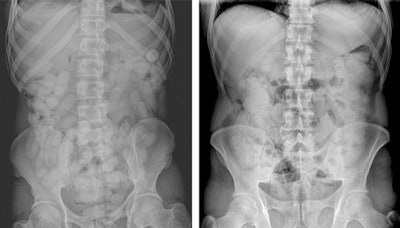

Initial modalities for detection of any drugs concealed within the body include x-ray, and ultrasound, but these are sometimes insufficient and can yield false-negative and false-positive results, while other legal and ethical considerations must also be factored into attempts at diagnosis.

"Detection of packets filled with liquid cocaine via plain film and ultrasound is more difficult than those filled with solid drugs. Furthermore, drug mules try to disturb exams by rapid breathing or moving. Suspects are also protected against unnecessary examinations and high-dose radiation," noted Bulakçı, who specializes in body imaging and nonvascular interventional radiology. "Studies show that nonenhanced CT can yield 100% success rates for the detection of solid and liquid drugs. That said, the efficacy of CT in body stuffers is not yet clear as there are just a few papers on this issue."

In each radiological examination method, it is important to know how packets containing different materials can be visualized. For example, liquid cocaine is radiopaque with thin lucent lines on plain film, and on ultrasound has a hyperechoic irregular surface with clean shadow. However, on CT it appears hyperdense with thin hypodense lines and a specific jigsaw pattern.